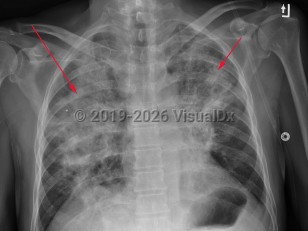

Fever, Cough, 50-59 year old Female

COVID-19

InfluenzaInfluenza